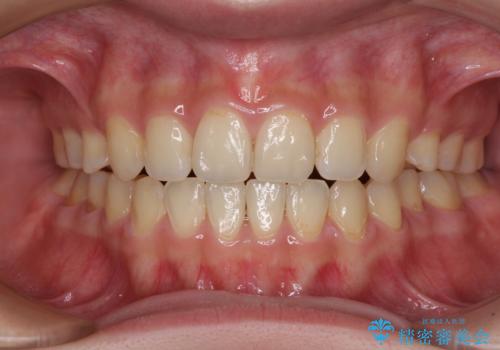

上下前歯が接触しない オープンバイトをインビザラインで改善

オープンバイト(開咬)を非抜歯インビザラインで治す